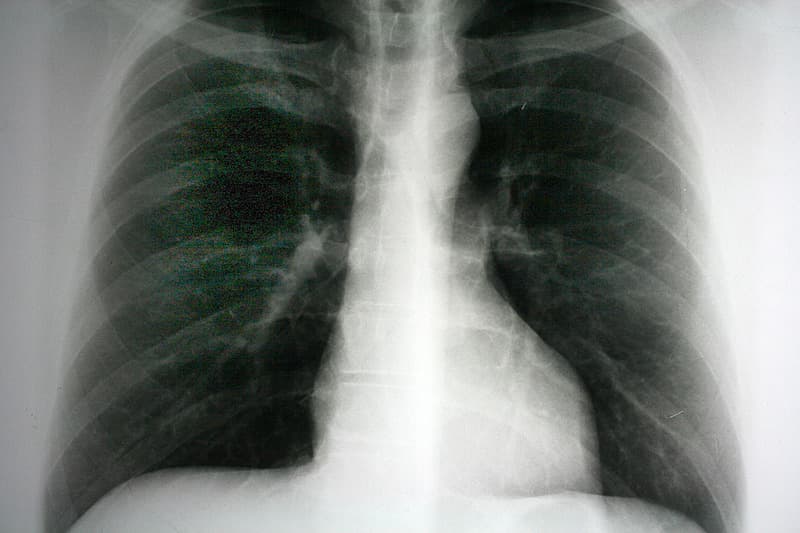

Mange patienter med svært emfysem har til trods for maksimal medicinsk behandling svær åndenød ved fysisk anstrengelse. Den vigtigste patofysiologiske mekanisme er hyperinflation af brystkassen, som fører til øgning af vejrtrækningsarbejdet. Ved at enten fjerne eller kollabere det emfysematiske lungevæv kan man genoprette brystkassens form og diafragmas placering. Nyt systematisk review af lungevolumenreduktion til patienter med svært emfysem medtager 18 randomiserede studier med næsten 2.800 patienter, som blev behandlet med enten kirurgi, indsættelse af ventiler eller coils eller ved brug af skleroserende stoffer, og konkluderer, at disse indgreb på kort sigt fører til betydende forbedringer i de lungefysiologiske parametre, patienternes livskvalitet og funktionsniveau, men viser også en relativ høj postoperativ morbiditet.